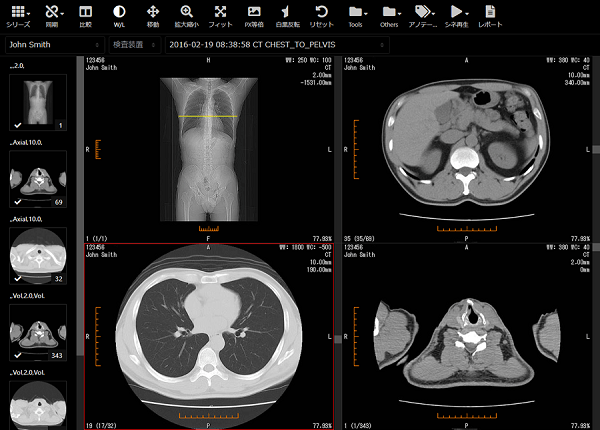

本製品は、CRやCT、MRIなどの検査装置から発生するデジタルな医用画像データを保管、管理し、それらの画像をWebブラウザで参照することができるソフトウェアです。2018年の販売開始以来、Webブラウザベースの高速画像ビューアを搭載し、リーズナブルなコストで導入できることから、高い評価を得ています。